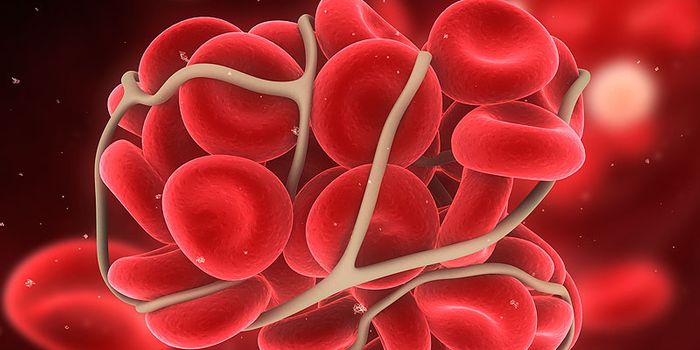

DEC 12, 2013MicrobiologyThe phrase "blood clot" rarely has a positive spin-most people associate blood clots with traumatic and potentially fata ...

NOV 09, 2017CardiologyBlood clots are normally seen as something to be avoided, something with dangerous consequences such as heart attack, st ...

SEP 17, 2020Clinical & Molecular DXBlood clotting, also known as coagulation, is a critical biological mechanism to prevent excessive blood loss in the eve ...

MAY 25, 2017CardiologyThe development of a blood clot could be very beneficial or very dangerous, depending on the situation. On one ha ...